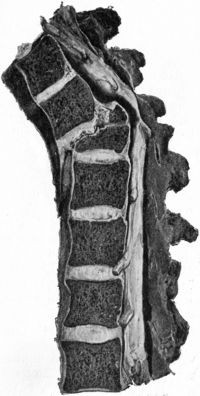

429 210.Tuberculous Osteomyelitis affecting several Vertebræ at Thoracico-Lumbar Junction

432 211.Osseous Ankylosis of Bodies (

a) of Dorsal Vertebræ, (

b) of Lumbar Vertebræ following Pott's Disease